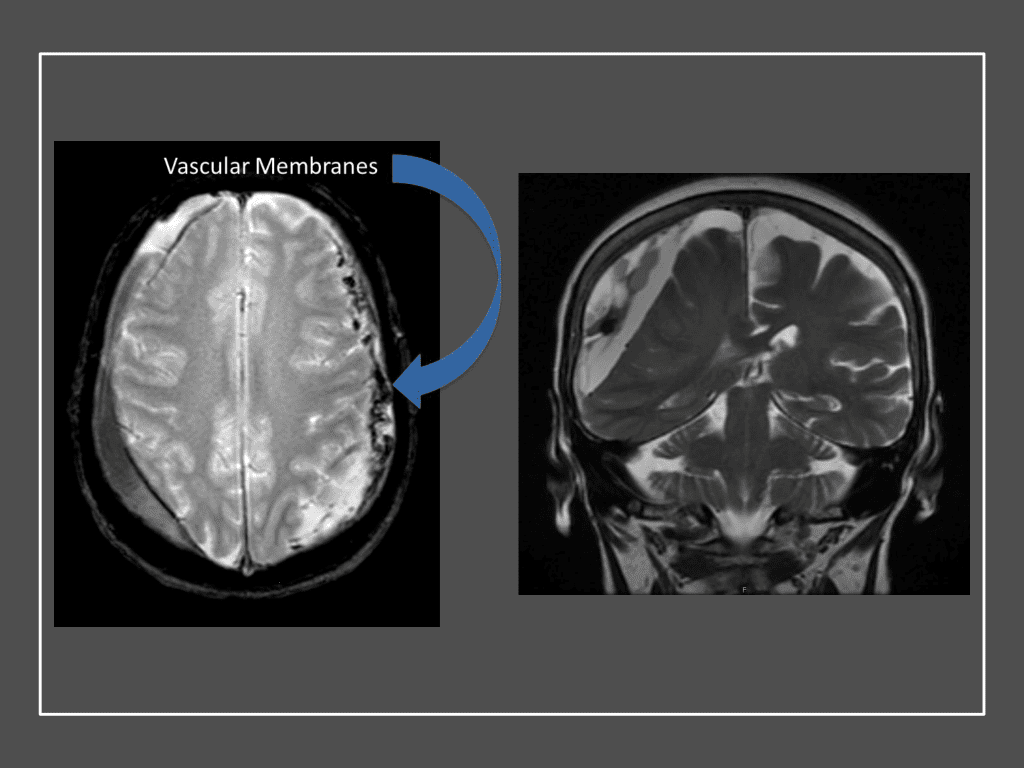

Although conventional surgical methods, such as burr hole irrigation or observation in asymptomatic or minimally symptomatic patients have been the mainstay of treatment, middle meningeal artery (MMA) embolization has emerged as a promising adjunctive or alternative treatment. MMA embolization is a neuroendovascular technique which involves placing a microcatheter into the Middle Meningeal Artery, most commonly on the side of the cSDH (occasionally, bilateral embolization has been recommended for larger or bilateral collection. Embolization of both the anterior (frontal) and posterior (parietal) division is performed using a variety of embolic materials (liquid NBCA, Onyx, coils), although polyvinyl alcohol particles of <250 microns are most commonly used to achieve distal penetration and occlusion of the pre-capillary and capillary beds. The micro-leakage of blood and transudative proteinaceous inflammatory fluid in these inflammatory membranes is creating an imbalance in cycle of resorption and preventing resolution or promoting recurrence or growth of these cSDH collections and associated mass effect and midline shift.

Figure 7. Neovascularized membranes within cSDH

Figure 8. Dense contrast staining of vascular membranes during embolization.